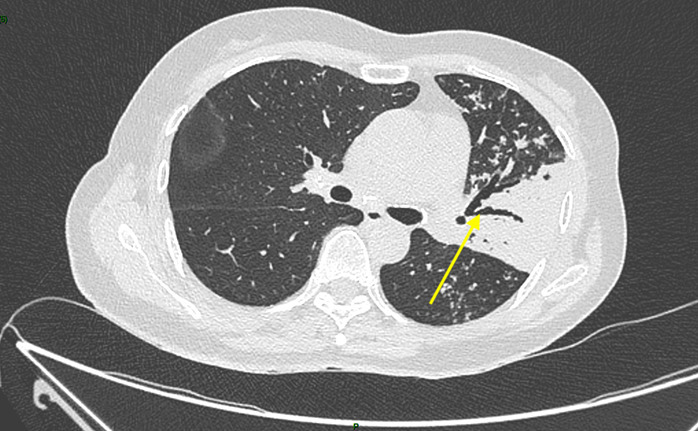

Un scanner thoracique est finalement réalisé devant cette toux chronique et l’altération de l’état général, dont voici quelques coupes :

Figure 2 (Jacques Durin, La Revue du Praticien)

Aspect de pneumopathie avec une condensation lobaire supérieure gauche et la présence d’un bronchogramme aérien dessinant l’arbre bronchique (flèche jaune).

Absence de liquide au contact de la condensation, pas de pleurésie déclive.

Le compte-rendu de radiologie décrit un aspect de pneumopathie lobaire supérieure gauche associée à des micronodules péri-bronchiolaires et des adénopathies médiastino-hilaires calcifiées.